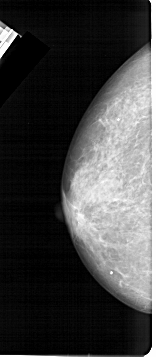

A_1473_1.RIGHT_MLO

RIGHT_MLO LINES 5491 PIXELS_PER_LINE 2296 BITS_PER_PIXEL 12 RESOLUTION 43.5 OVERLAY